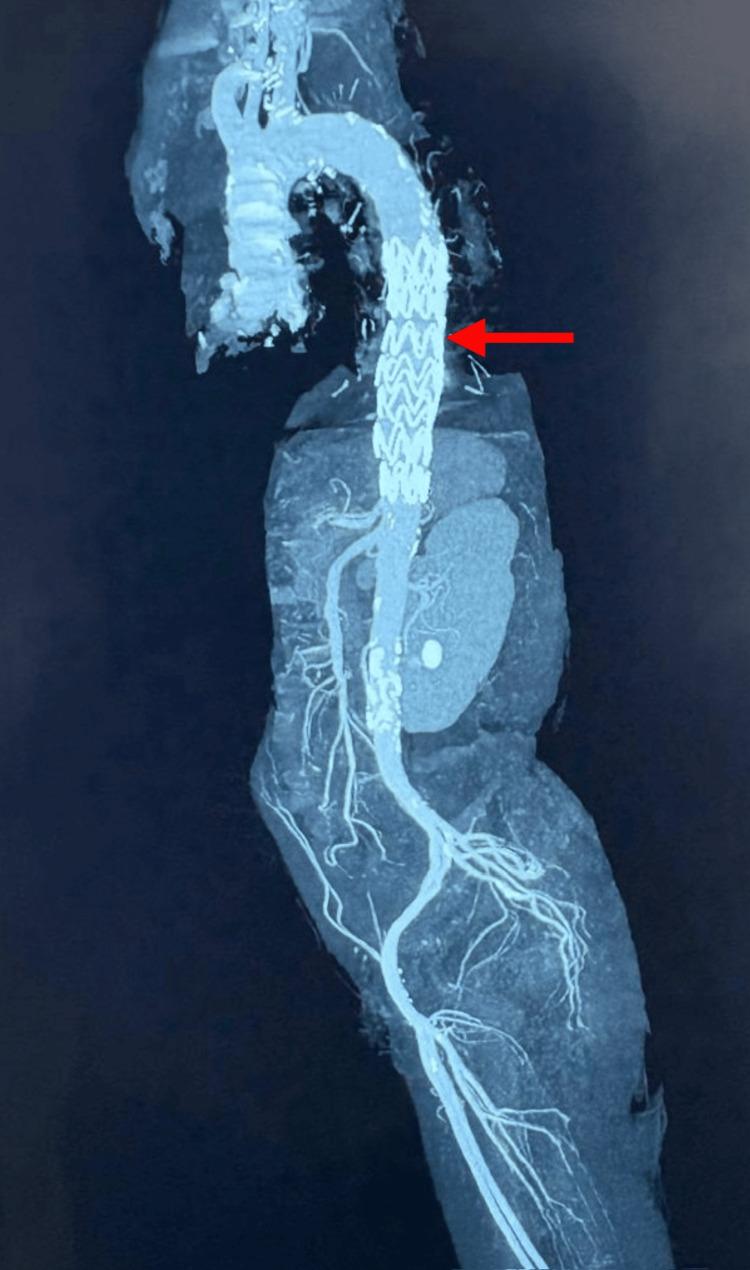

The rupture of a descending thoracic aortic aneurysm (DTAA) is a rare but critical vascular emergency that requires immediate recognition and action. It usually presents as a sharp, severe pain in the chest or back; however, some individuals exhibit non-typical symptoms resembling respiratory infections, leading to misdiagnosis and delays in definitive treatment. A 63-year-old male with a history of hypertension and smoking presented with left-sided chest pain to another hospital, where he was diagnosed with unstable angina based on clinical suspicion and managed conservatively with anti-anginal medication. Over the next three days, the patient developed a persistent cough, low-grade fever, and pleuritic pain, prompting referral to our hospital, where a lower respiratory tract infection (LRTI) was considered. On arrival, he was hemodynamically stable with a systolic BP of 100 mmHg and was managed with intravenous fluids, antibiotics, and nebulizers. Chest X-ray revealed moderate left pleural effusion with tracheal deviation, and thoracic ultrasound confirmed internal echoes suggestive of hemorrhagic content. Diagnostic thoracentesis yielded hemorrhagic fluid, prompting high-resolution computed tomography (HRCT), which showed a partially thrombosed 54 mm × 49 mm saccular aneurysm of the descending thoracic aorta with left lung collapse. Despite the rupture, the patient remained hemodynamically stable, suggestive of a contained event. A subsequent computed tomography angiogram (CTA) confirmed rupture into the pleural space and was the imaging modality that established the final diagnosis. The patient underwent thoracic endovascular aortic repair (TEVAR) using a 30 mm × 30 mm × 120 mm Ankura graft, selected for its conformability and effective sealing profile in emergencies. Postoperative recovery was uneventful. A CT aortogram on day three confirmed complete exclusion of the aneurysm with no endoleak, and a follow-up chest X-ray at two weeks showed full resolution of the hemothorax. This case illustrates the diagnostic challenge posed by atypical ruptured DTAA presentations and reinforces the importance of early CTA in unexplained pleural effusions, even in stable patients. Structured post-TEVAR surveillance remains critical to ensure long-term outcomes.

降主动脉瘤(DTAA)破裂是一种罕见但危急的血管急症,需要立即识别并采取行动。其通常表现为胸部或背部突发剧痛;然而,一些患者会出现类似呼吸道感染的非典型症状,导致误诊及确定性治疗延误。一名63岁男性,有高血压和吸烟史,因左侧胸痛前往另一家医院就诊,基于临床怀疑被诊断为不稳定型心绞痛,并接受抗心绞痛药物保守治疗。在接下来的三天里,患者出现持续咳嗽、低热和胸膜炎性疼痛,遂转诊至我院,当时考虑为下呼吸道感染(LRTI)。入院时,他血流动力学稳定,收缩压为100 mmHg,接受了静脉输液、抗生素和雾化治疗。胸部X线显示左侧中等量胸腔积液伴气管偏移,胸部超声证实内部回声提示为血性成分。诊断性胸腔穿刺抽出了血性液体,促使进行高分辨率计算机断层扫描(HRCT),结果显示降主动脉有一个54 mm×49 mm的部分血栓形成的囊状动脉瘤,伴左肺萎陷。尽管已经破裂,但患者血流动力学仍保持稳定,提示为局限性事件。随后的计算机断层血管造影(CTA)证实动脉瘤破裂进入胸腔,这一成像方式确立了最终诊断。患者接受了胸主动脉腔内修复术(TEVAR),使用了一枚30 mm×30 mm×120 mm的安珂拉移植物,选择该移植物是因其顺应性好且在紧急情况下具有有效的密封性能。术后恢复顺利。术后第三天的CT主动脉造影证实动脉瘤完全被隔绝,无内漏,术后两周的胸部X线随访显示血胸完全吸收。该病例说明了非典型破裂DTAA表现所带来的诊断挑战,并强调了早期CTA在不明原因胸腔积液中的重要性,即使是在病情稳定的患者中。TEVAR术后的结构化监测对于确保长期疗效仍然至关重要。